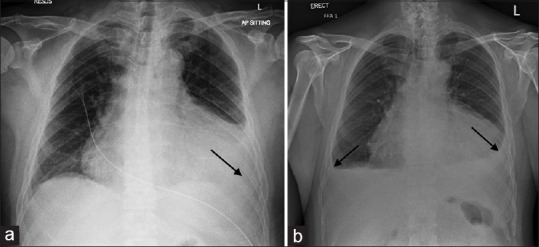

Acute pericarditis and cardiac tamponade after COVID-19 vaccination.

接种 Covid-19 疫苗后出现急性心包炎和心脏填塞。